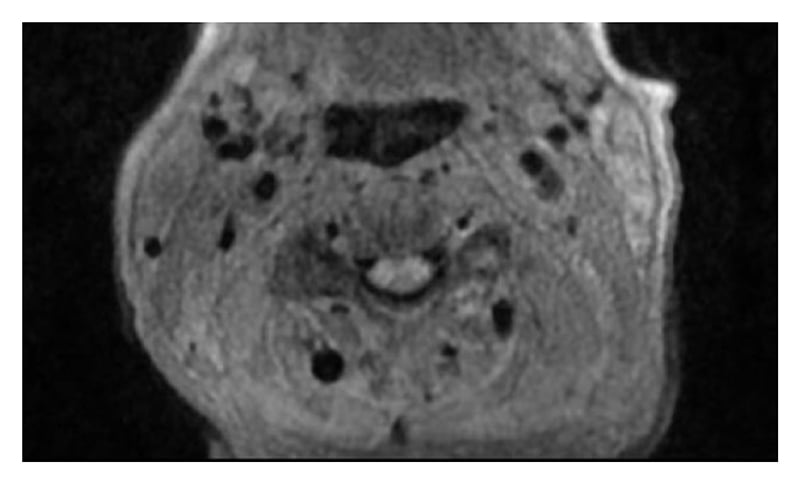

Magnetic resonance angiography (MRA) of the head and neck showed soft-tissue thickening of the distal left common carotid artery and left carotid bifurcation (Figure 1). A positron emission tomography (PET)-CT scan identified asymmetric moderate activity of the tracer fluorodeoxyglucose (FDG) along the medial aspect of the left common carotid artery (Figure 2). Skipped areas of mild uptake were also noted along the thoracic aorta wall.

Figure 1: MRA of the neck shows soft-tissue thickening and enhancement surrounding the distal left common carotid artery and left carotid bifurcation without stenosis.